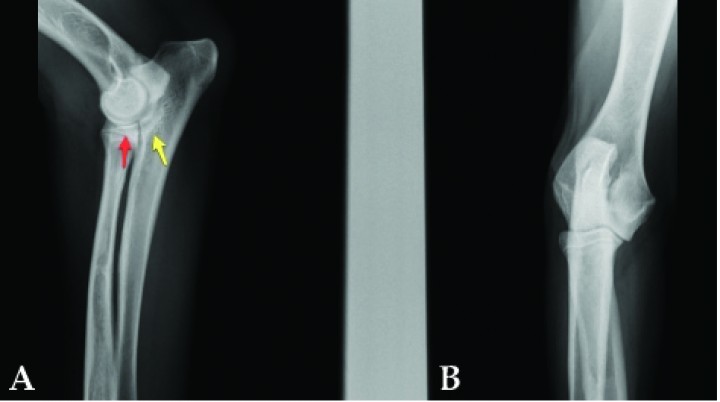

El diagnóstico presuntivo de la displasia de codo y el estudio de la graduación de la misma en la mayoría de animales fue realizado a través de la radiología (Fig. 5).

<p>Radiografía lateral de un Labrador de 11 meses donde se observa una marcada esclerosis subtroclear (flechas amarillas) y difuminación del borde del proceso coronoideo (flechas rojas) indicativas de enfermedad del compartimento medial.</p>

Figura 5

Radiografía lateral de un Labrador de 11 meses donde se observa una marcada esclerosis subtroclear (flechas amarillas) y difuminación del borde del proceso coronoideo (flechas rojas) indicativas de enfermedad del compartimento medial.

De acuerdo con el Grupo Internacional para el Estudio del Codo (I.E.W.G), el hallazgo de artrosis en el codo de un animal en crecimiento es patognomónico para el diagnóstico de DC.[ Ondreka, N., Tellheim, B. Explanation of grading according to IEWG and discussion of cases. IEWG proceedings, Verona, August 2017, 33-34. ] Sin embargo, en muchas ocasiones, radiografías casi normales pueden esconder grandes cambios displásicos en el interior articular[ Punke JP1, Hulse DA, Kerwin SC, Peycke LE, Budsberg SC. Arthroscopic documentation of elbow cartilage pathology in dogs with clinical lameness without changes on standard radiographic projections. Vet Surg. 2009;38(2):209-12. [PubMed] ] (Fig. 6). Asimismo, se ha demostrado que no existe correlación entre la severidad de los signos radiológicos y los daños en cartílago y hueso subcondral evaluados artroscópicamente en una serie de 263 casos de PCF.[ Fitzpatrick N, Smith T, Evans R, et al. Radiographic and arthroscopic findings in the elbow joints of 263 dogs with medial coronoid disease. Vet Surg 2009; 38: 213-223. [PubMed] ]

<p>(<strong>A</strong>) Radiografía lateral de un Golden Retriever de 8 meses. (<strong>B</strong>) Radiografía craneocaudal. Se aprecia una muy leve esclerosis subtroclear (flecha amarilla) y definición normal del ápex del coronoides (flecha roja). El animal se trató de forma conservadora hasta que el grado de cojera aconsejó la intervención (véase Fig. 9A).</p>

Figura 6

(A) Radiografía lateral de un Golden Retriever de 8 meses. (B) Radiografía craneocaudal. Se aprecia una muy leve esclerosis subtroclear (flecha amarilla) y definición normal del ápex del coronoides (flecha roja). El animal se trató de forma conservadora hasta que el grado de cojera aconsejó la intervención (véase Fig. 9A).